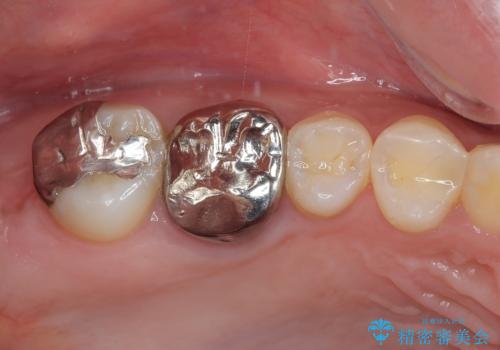

しかし、噛み合わせの相手である右上の第二大臼歯が、長期間噛み合う歯がなかった影響で**挺出(歯が下に伸びてくる状態)してしまっており、このままではインプラントを埋入して被せもの(上部構造)を入れるためのスペースが不足している状態でした。

その後、挺出していた右上第一大臼歯と第二大臼歯に装着されていた銀歯についても、審美性と適合性の向上を目的に、オールセラミッククラウンにやり替えました。